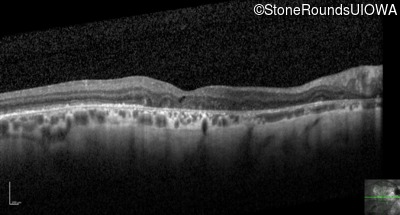

Optical Coherence Tomography - Left - 20/200

Exemplar / OCT Stack